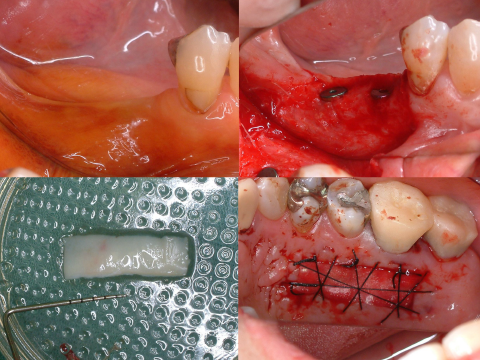

矯正的挺出終了時の口腔内写真及びデンタル

矯正的挺出終了時の口腔内写真及びデンタル写真です。

レントゲン上で目標とする挺出量がかくとくできたので、この段階で歯周形成外科を行うことにしました。

術前および術後の比較

before before |

after after |

矯正治療開始前及び矯正治療終了時の口腔内写真とレントゲン写真です。

歯肉形成外科の術中所見です。最終的は被せもののイメージを行いながら歯茎と顎の骨の整形を行いました。

before before |

after after |

術前と術後の比較写真です。

歯茎の下の方まで虫歯でしたが歯茎の上までしっかりと健康な歯の部分を出すことができました。

歯の形を整え最終的な被せもの被せた時の口腔内写真です。

before before |

after after |

術前、術後の比較写真です。

歯の保存と見た目の改善もでき、患者さんも満足してくださいました。